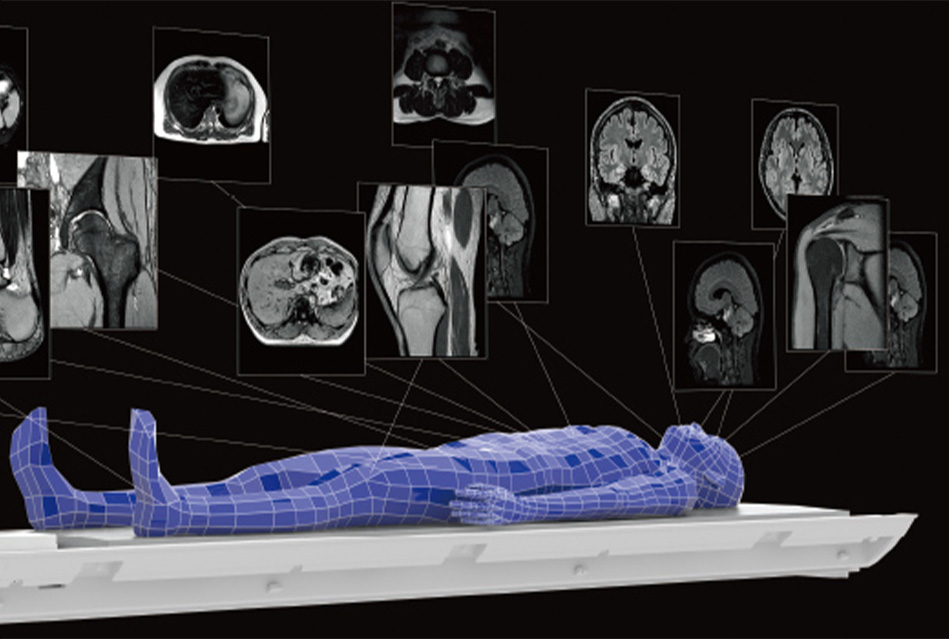

Сучасні приймальні котушки

✓ FlexFit Neuro (голова та шия)

✓ FlexFit Wide (720 × 545 мм)

✓ Механізм нахилу для комфортного позиціонування

Котушки забезпечують щільний контакт з пацієнтом та покращення SNR.

- Автоматичне сканування